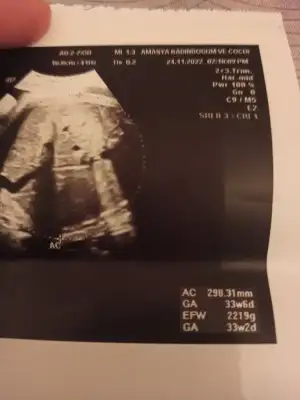

Gözün Aydın canım inşallah bir an önce bebeğinle kavuşup evinize geçersiniz sağlıkla büyüsünSelam kızlar, bugün 37+5ken sezeryanla geldi minik kızım 2880 Gr,49 santimmis, suyum tamamen bitmiş ilginç bir şekilde ,bebeğimin de nefes alış verişi biraz hızlı imiş , doktor biraz rahatlasın diye kuvoze almış , benim uyuşuklugum geçince yanına ineceğim görmek için , ins çabuk toparlar kavuşuruzspinal anestezi ile oldu doğum anı bence çok rahattı bebeğim cikisina şahit olmak çok güzel sesini de duydum orda